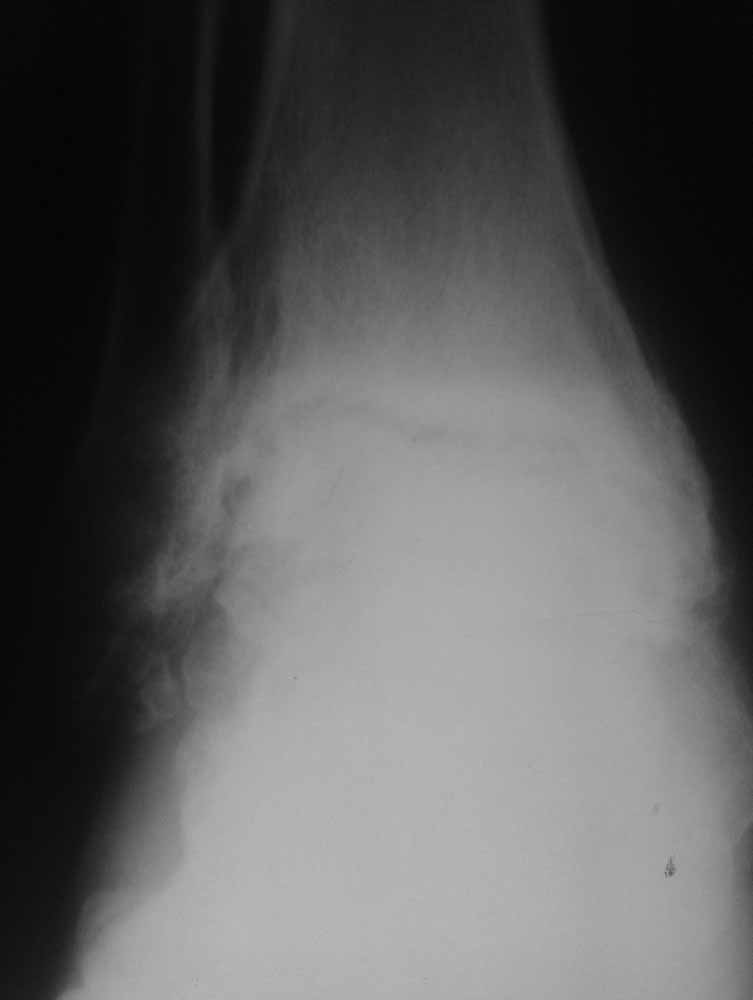

Зачем вытяжение - эффект на рентгенограммах виден.

Склоняемся к мысли, что все таки Charcot's Joint.

Планируем артродез стержнем правого голеностопа + аппарат на левый голеностоп.

Остается вопрос - как монтировать ? одномоментно корректировать или все таки постепенно аппаратом?